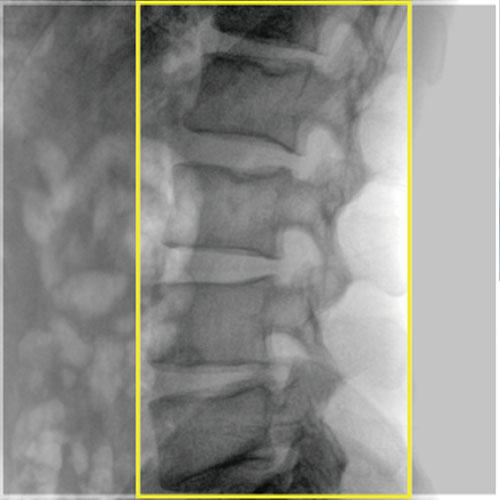

Large dynamic FPD with smaller pixel size, ensuring distortionless imaging; Wider FOV, avoiding overlapping and omissions, reducing exposure time and radiation dose, and shortening the operation time.

More than doubled imaging area

Meeting the surgical needs of about 80% large DSA equipment